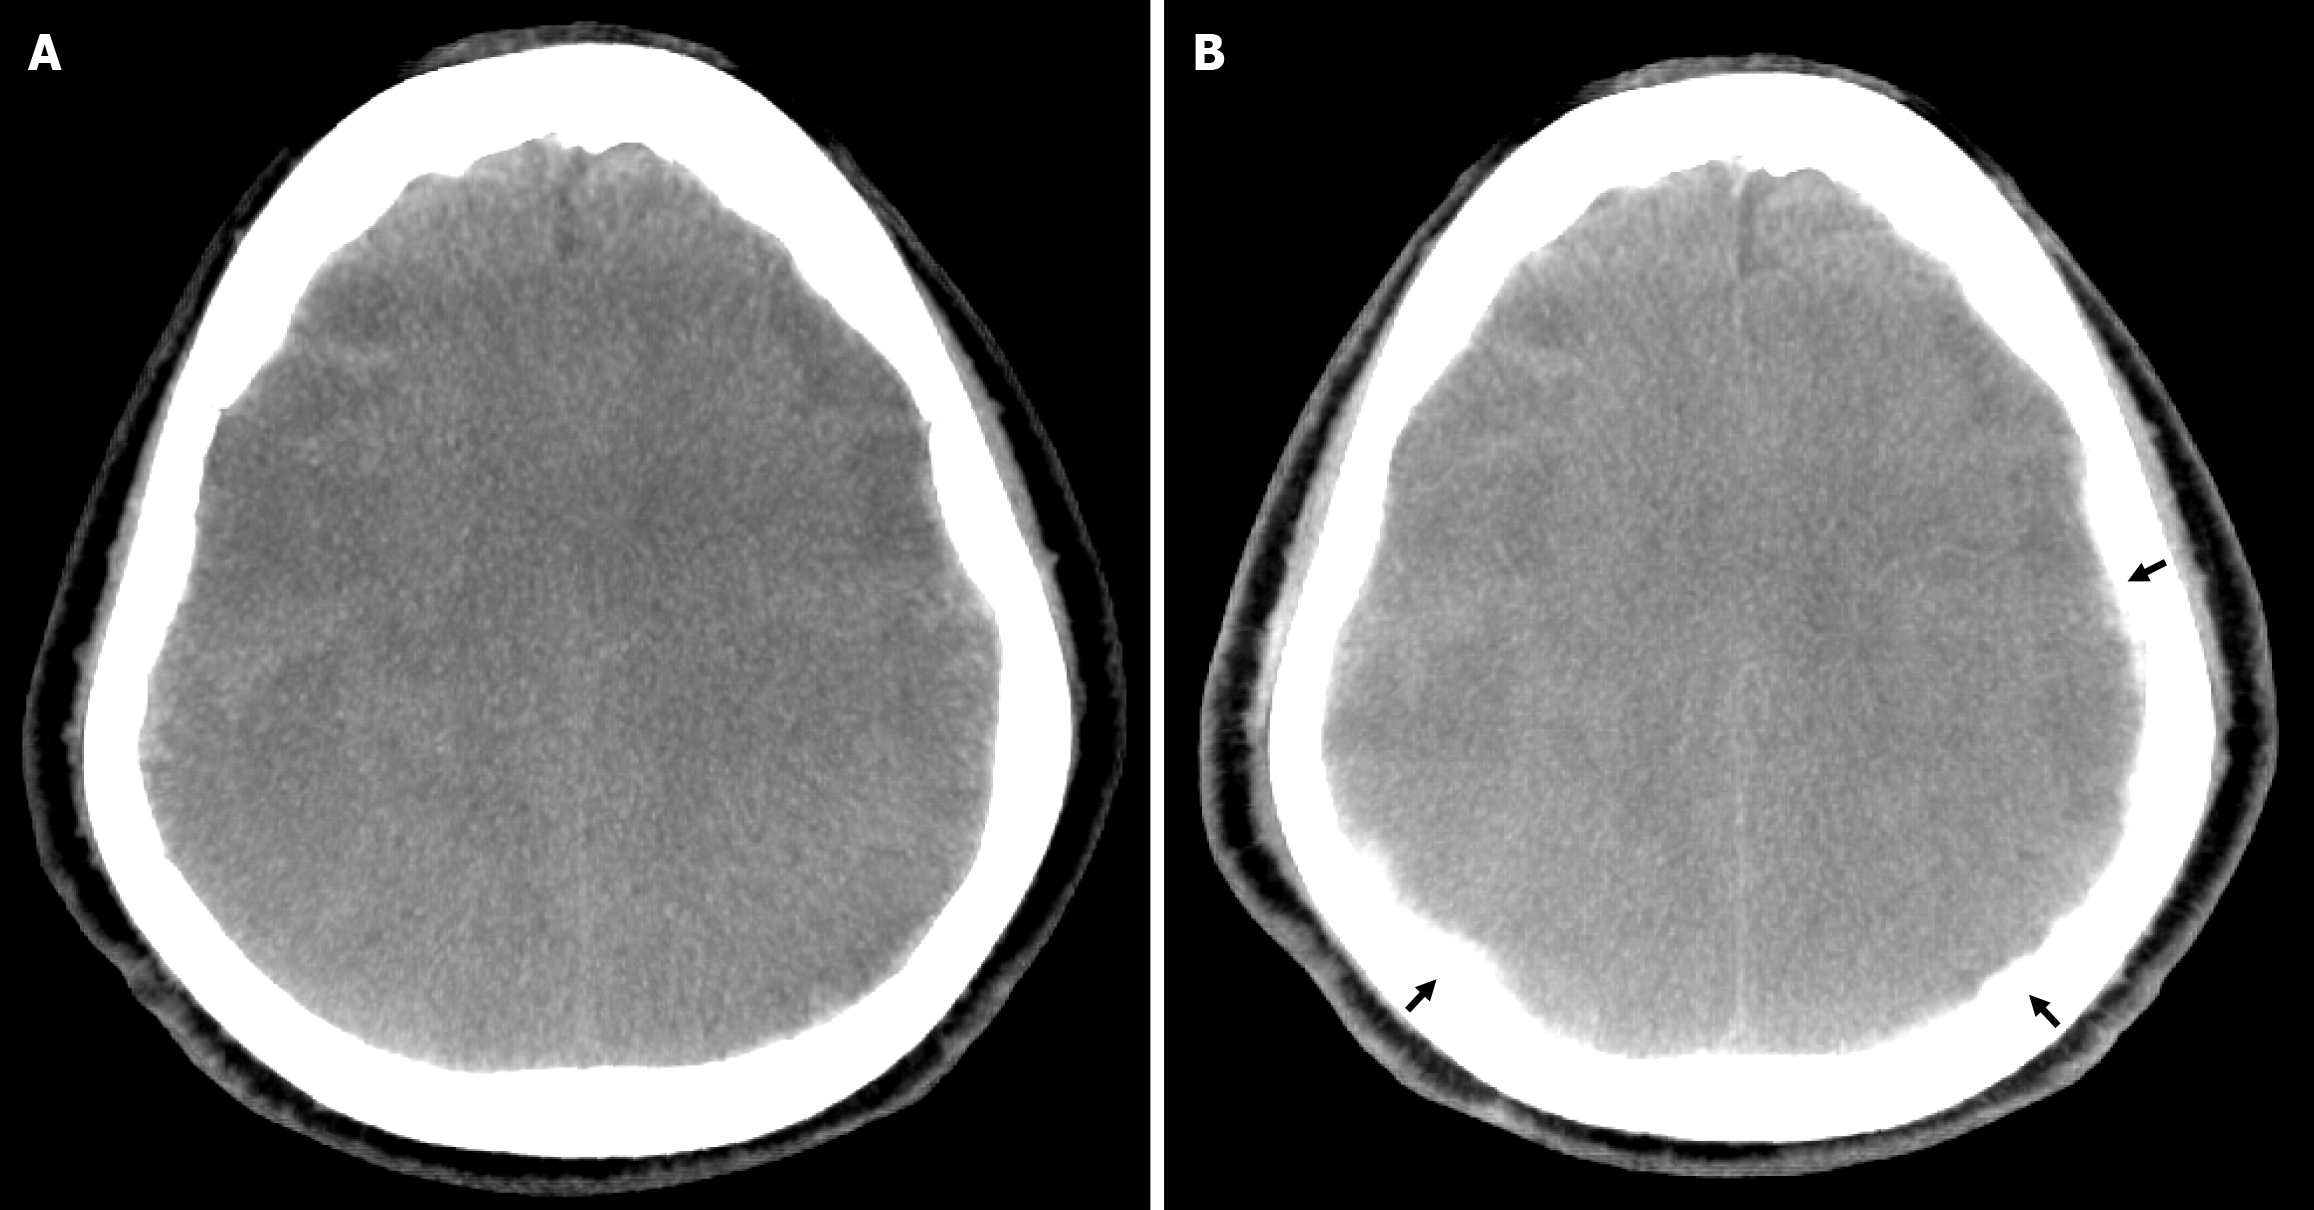

Brain computed tomography (CT) demonstrated bilateral cSDH with mass effect (3.3 cm on the right and 1.64 cm on the left). Selective pre-embolization angiography of the middle meningeal artery (MMA) revealed the anterior and posterior branches supplying the external membranes of the hematomas, demonstrating a contrast blush indicative of pathological neovascularization (Figure 1).

The injection proceeded under continuous fluoroscopic guidance until complete vessel stasis was confirmed angiographically. Intraprocedural cone-beam CT following MMAE demonstrated contrast penetration into the subdural space (Figure 2), consistent with deposition of PVA particles.

Follow-up CT scans at 1, 2, and 3 months post-procedure showed complete hematoma resolution and significant brain re-expansion (Figure 3). No procedure-related complications occurred.